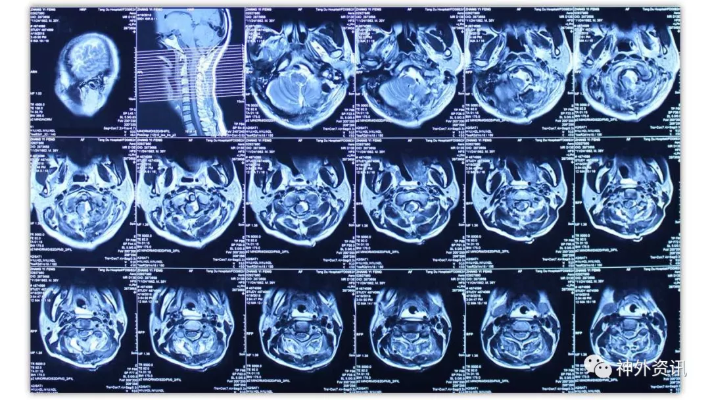

经乙状窦后联合远外侧入路切除岩斜-枕骨大孔-颈2脑膜瘤一例